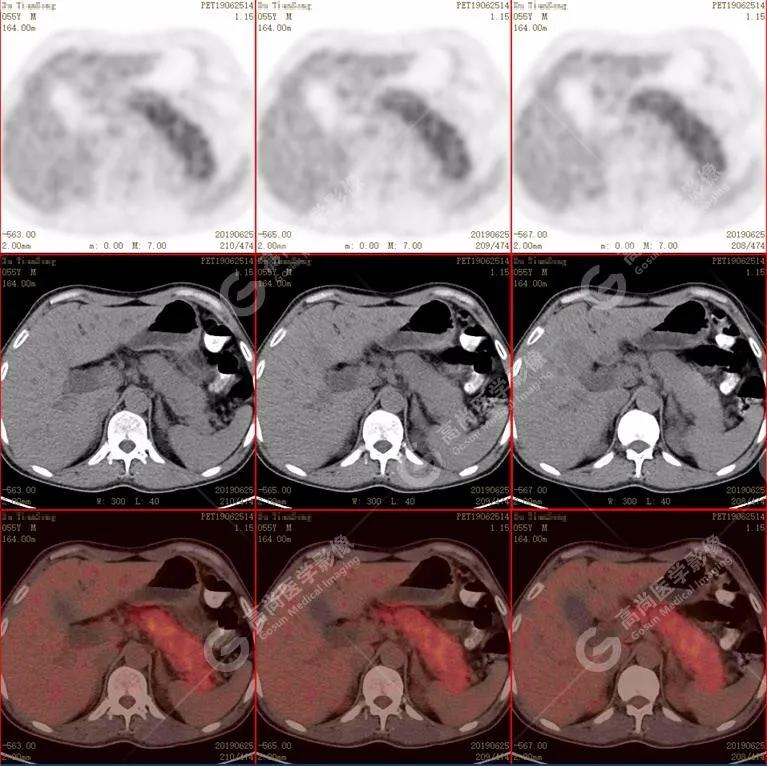

胰腺肿胀、密度均匀,代谢弥漫性不均匀增高,SUV最大值5.2 平均值4.0

(1)胰腺轻度肿胀,胰腺体尾部胰管狭窄,未见明显占位性病变,代谢弥漫性增高。

• PET/CT:多呈弥漫性代谢增高,少数呈局灶性结节状高代谢灶。

•CT:胰腺体积 不同程度弥漫性肿大 ,密度减低或正常,增强扫描动脉早期强化低于正常胰腺,延迟期 均匀一致强化。胰周脂肪间隙多数清晰 ,少数可见少量条状异常密度或信号(轻度炎性反应)。